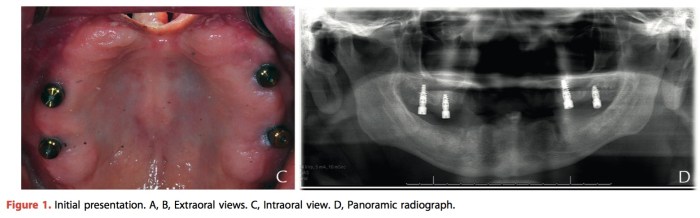

這篇文章是去描述一個上顎前半部以及鼻子因為癌症切除而製作補綴物重建的案例。你說為什麼我們台灣類似這樣的case少?不是少,我個人覺得有兩大原因,第一:這類的患者多半社經地位不佳,根本就沒有錢可以植牙。第二,做free flap補起來有健保,做假牙?有surgical obturator 似乎5000點,跟咬合板一樣,那我乾脆不要做因為陪錢。這幾天又遇到一個類似的case,上顎整個要切掉只剩下zygoma可以用,我第一個反應就是那乾脆補肉然後插鼻胃管算了…